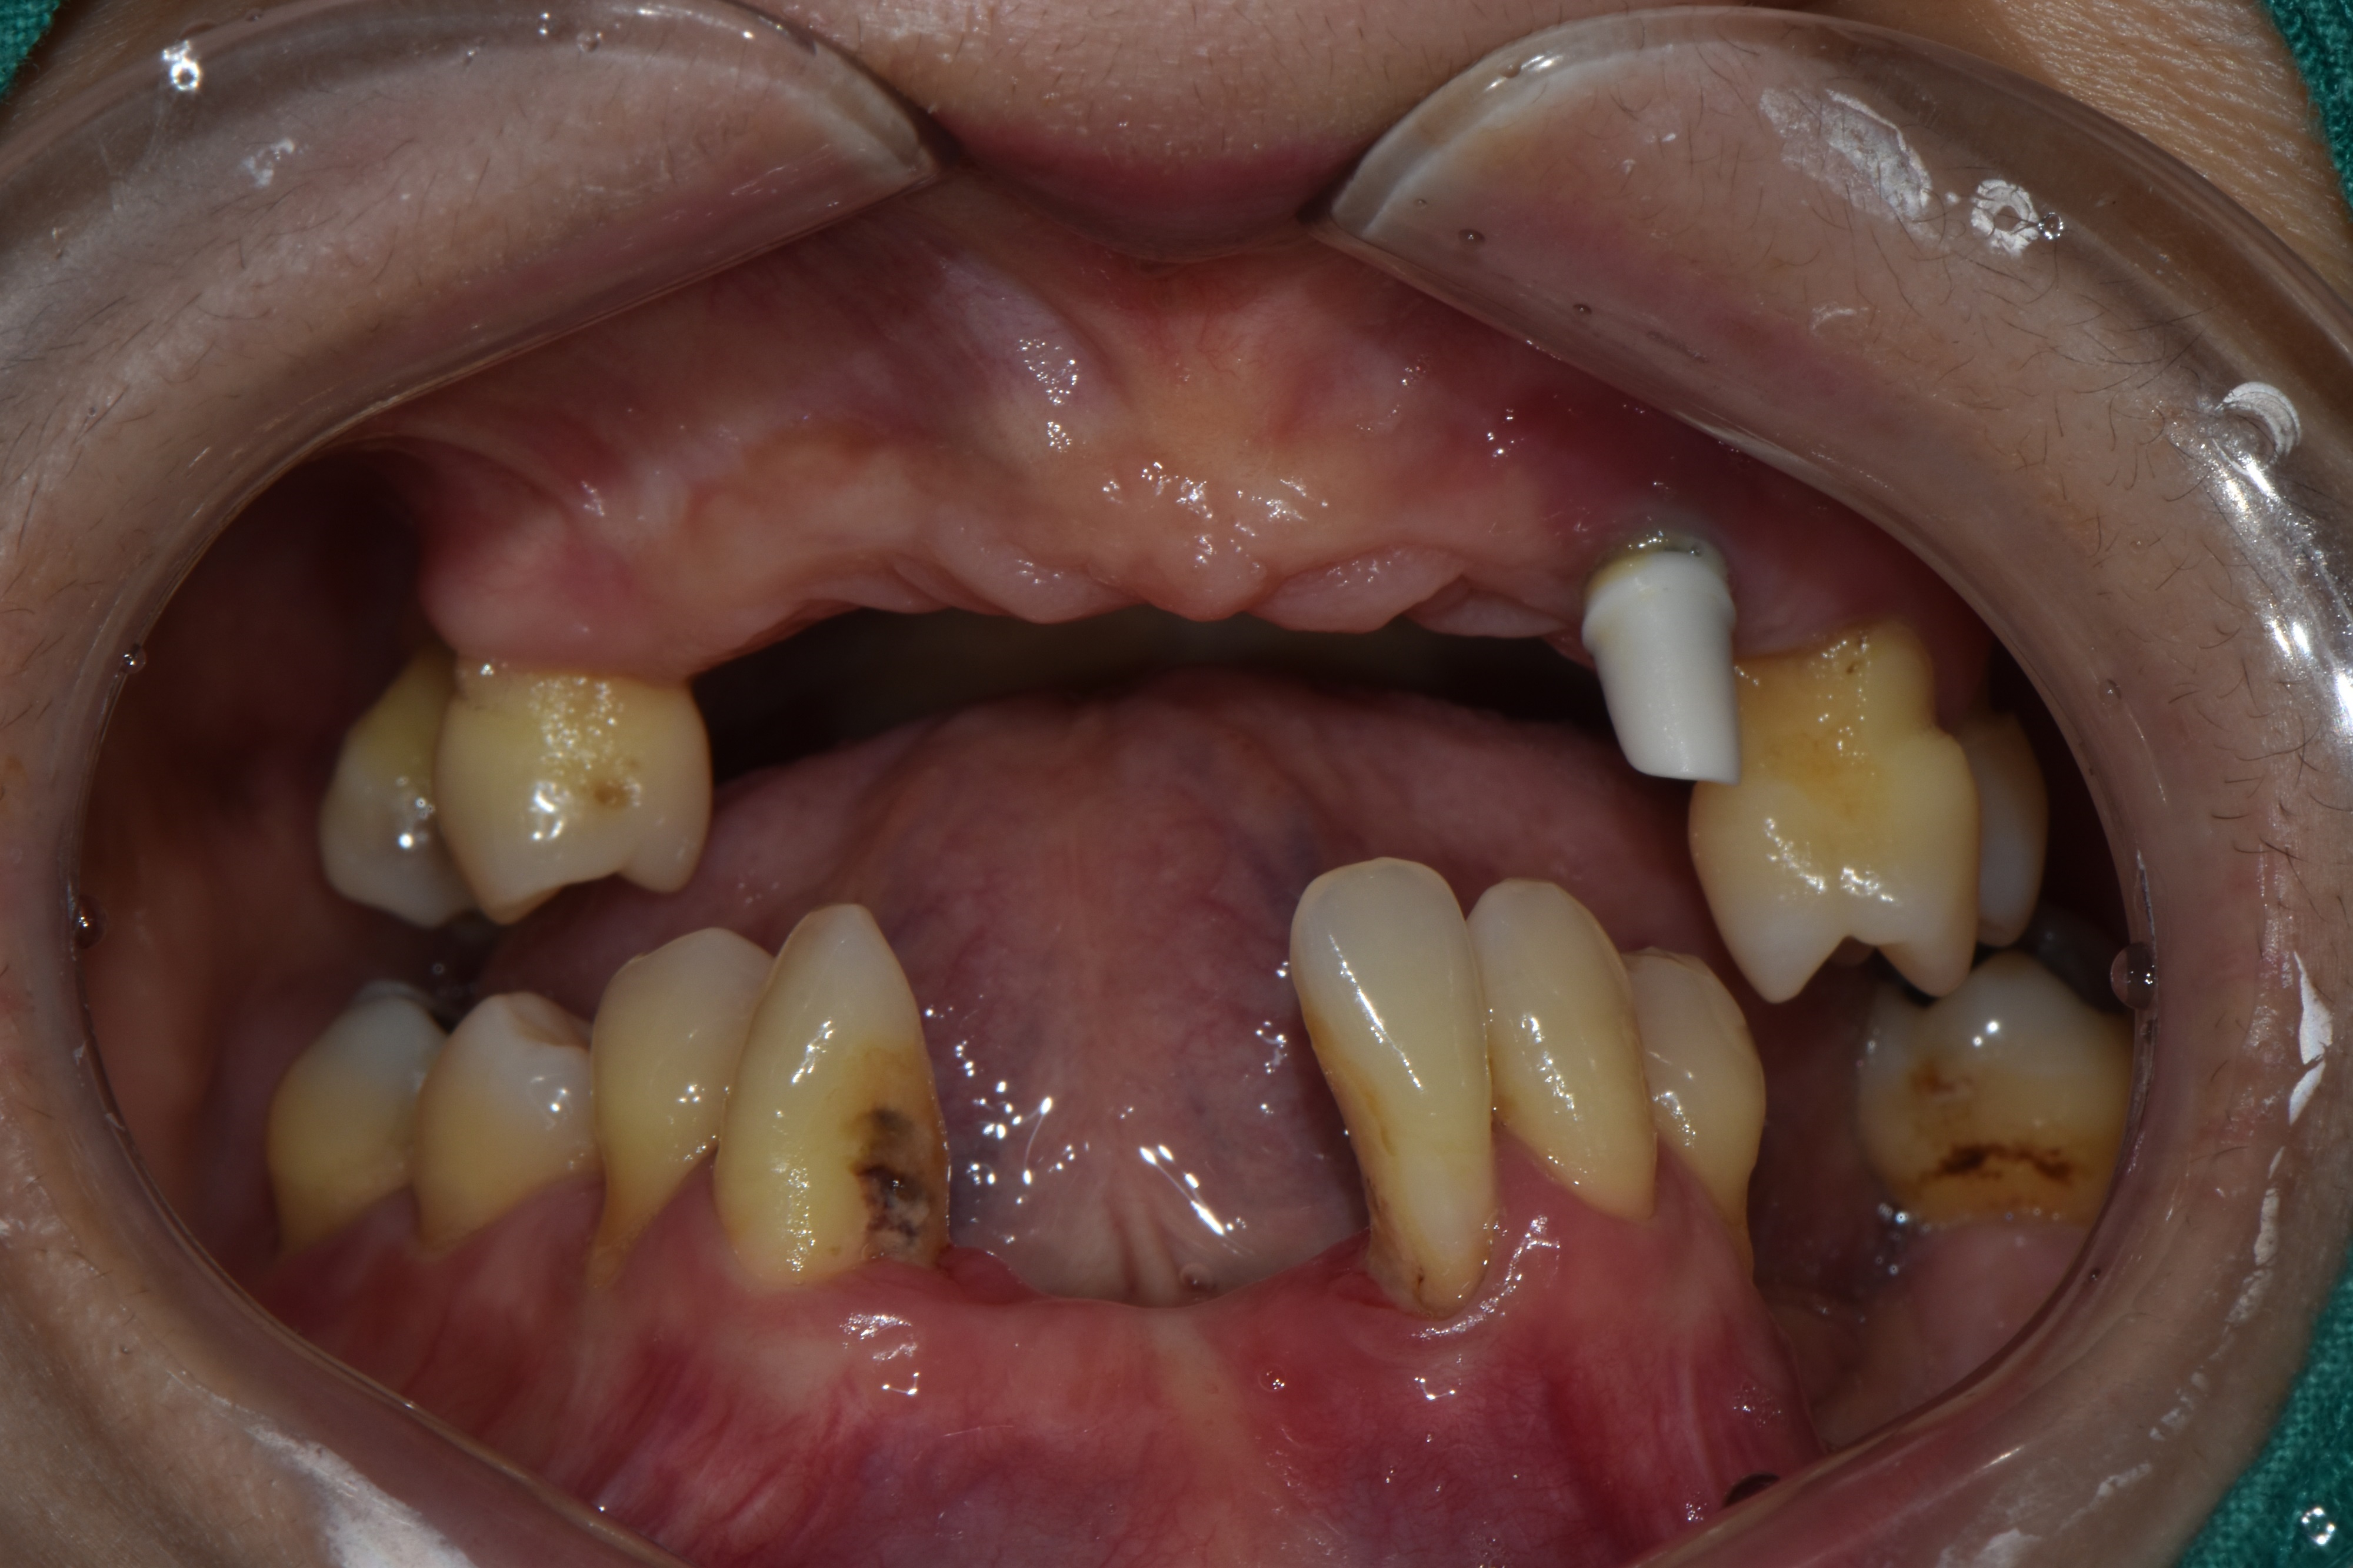

촬영일시: 2024.05.02